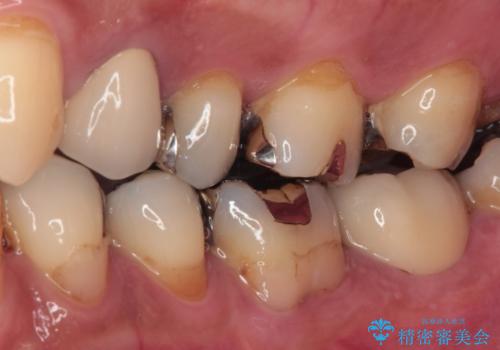

歯質の欠損が大きいため、処置後はオールセラミッククラウンにて補綴治療を行うこととしました。

後日状態を確認したところ、残された神経に異常は認められませんでした。